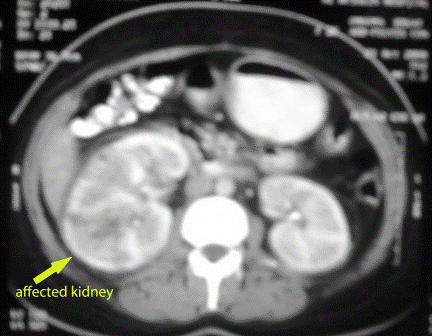

A female patient in her thirties, complained

of recurrent diabetic ketoacidosis, FOU, full investigations were done

without reaching to the actual cause of fever. In spite of many previous

normal abdominal ultrasonography, the last follow-up one revealed

enlarged right kidney, so CT scan was done and revealed the above photo.

However this picture confused us, the infectious nature of it was

strongly considered, so we considered it as a case of nephroma for which

the patient was given IV antibiotics for 2 weeks and then completed the

course by oral antibiotics for another 2 weeks.

She gave good response, the fever and constitutional symptoms subsided

also had controlled blood glucose levels with a decrease of the kidney

size